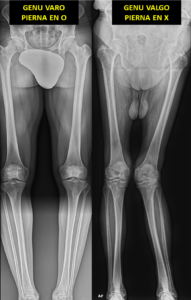

Dentro de las deformidades angulares de los miembros inferiores, las dos más frecuentes conocidas como genu varo y genu valgo, son alteraciones al mirar las piernas de frente donde vemos las piernas torcidas.

Genu Varo: Hace referencia a cuando las piernas están arqueadas, es decir, las rodillas se separan una de la otra. La pierna tiene forma de C o de paréntesis.

Genu Valgo: Es lo contrario, las piernas se cruzan como si las rodillas fueran a tocarse, son las piernas en forma de X.

Para valorar adecuadamente estas deformidades, los traumatólogos realizamos un tipo especial de radiografía llamada telerradiografía.